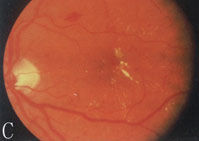

6、其他臟器併發症表現心血管病變如心力衰竭、心肌梗死。神經病變如周圍神經病變。累及自主神經時可出現神經源性膀胱。視網膜病變,糖尿病腎病嚴重時幾乎100%合併視網膜病變,但有嚴重視網膜病變者不一定有明顯的腎臟病變。當糖尿病腎病進展時,視網膜病變常加速惡化。

2.糖尿病視網膜病變和腎臟微血管病二者可同時存在。視網膜病變可繼發於糖尿病腎腎病以後,一般認為網膜病變的發生率高於腎微血管病變。因網膜病變易於觀察,而糖尿病腎腎病難於診斷,所以糖尿病人一旦出現網膜病變,要警惕腎病發生。